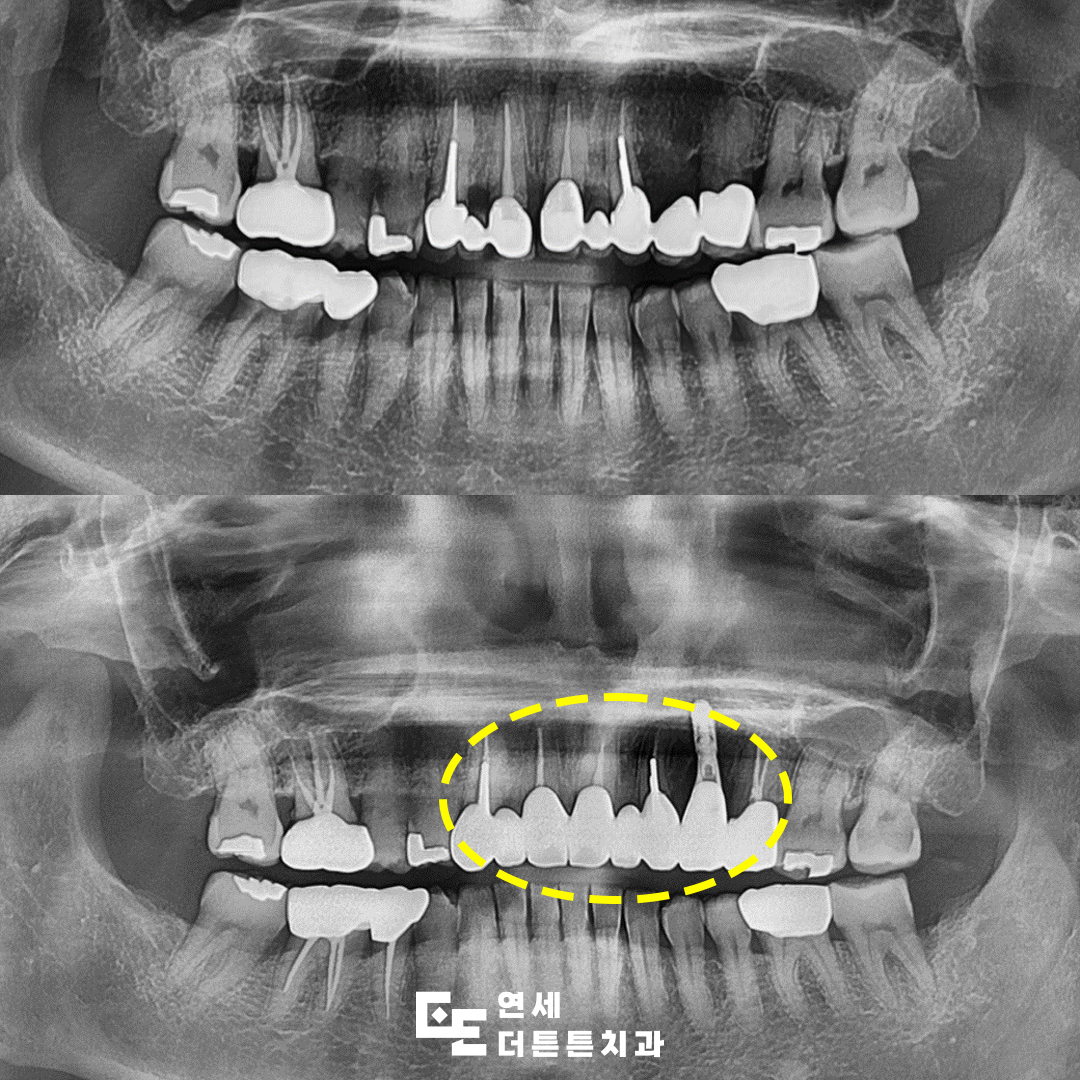

이번에는 오래전에 제작된 브릿지 보철물을 제거한 뒤 지르코니아 크라운을 이용해 재치료를 진행한 환자분의 사례를 중심으로 말씀드려보겠습니다. 환자분께서는 과거에 치료받은 앞니가

전체적으로 어둡게 보이고 인상이 좋지 않은 것 같다며 정밀 검진을 위해 내원해 주셨습니다. 송곳니부터 작은 어금니까지 넓게 연결된 형태는 아니었지만 당시 잇몸선에 맞춰 제작되다 보니 정면에서 보았을 때 앞니 사이의 잇몸 라인이 고르게 맞지 않아 심미적으로 아쉬움이 컸고, 보철물과 잇몸 사이에 틈이 생기면서 그 부분이 검게 비쳐 보이는 상태였습니다.

이에 기존 보철물을 모두 제거한 뒤 도봉동치과 앞니치료 계획에 따라 신경치료가 필요한 치아는 선행 치료를 진행하고 이후 재수복을 결정하게 되었습니다.